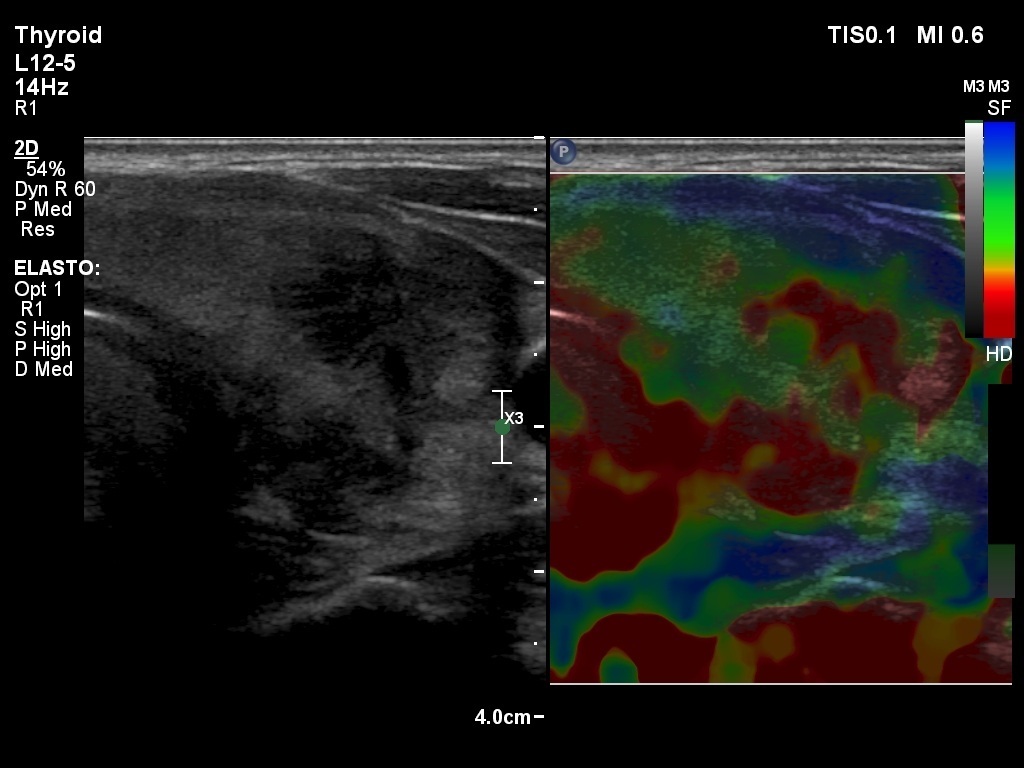

First examination (1st to 3rd rows of images):

Ultrasonography: Both lobes presented hypoechogenic ill-defined areas. The echogenicity index was 80% in the right lobe while 20% in the left thyroid. The vascularization was significantly decreased.

Elastography demonstrated hard areas according to the hypoechogenic field in the left lobe while almost the entire right lobe proved to be hard.Cytological diagnosis: subacute, granulomatous de Quervain's thyroiditis.